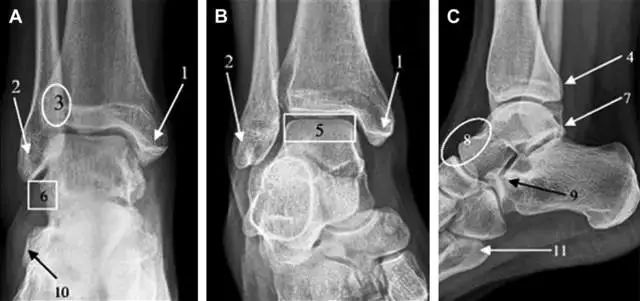

首先,来看踝关节骨折的高危区(图 1)。

图 1 踝部探查模板。阅片时,需对踝关节的前后位片(A)、内旋转位片(B)侧位片(C)仔细阅读,逐一详细排查。上图中的骨折:1. 内踝骨折,2. 外踝骨折,3. 胫骨结节骨折,4. 胫骨后踝骨折,5. 距骨骨软骨骨折,6. 距骨外侧突骨折,7. 距骨后突骨折,8. 距骨舟骨关节背侧骨折,9. 跟骨前突骨折,10. 跟骨骨折嵌插入趾短伸肌,11. 第五跖骨底骨折。